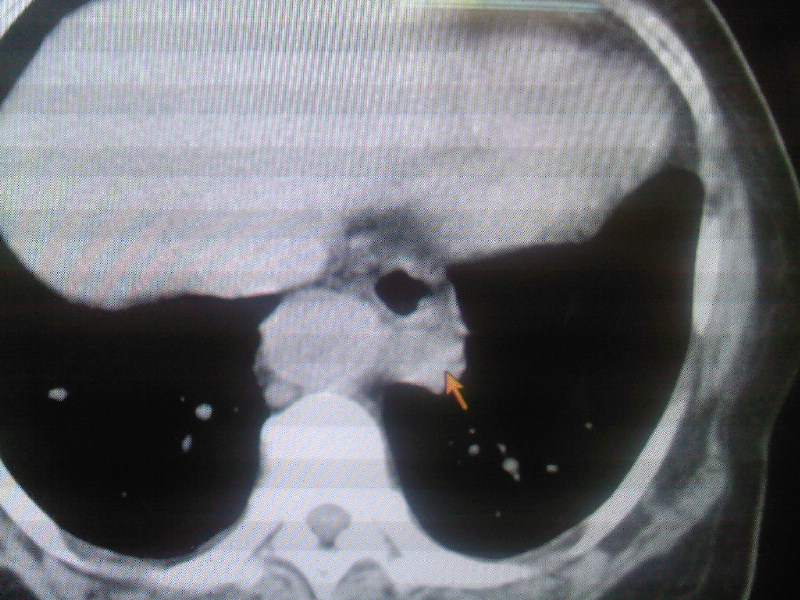

食管下段近贲门处可见前方一限局性空腔影。想临食管避受压,且与食管分界不清,跨与食管裂孔处,顶部位于中后纵膈,请指教

不排除溃疡型食道癌,吞钡看看。

食管癌?食管静脉曲张?建议行进一步检查。

症状与表现有差距,建议钡餐或镜检.